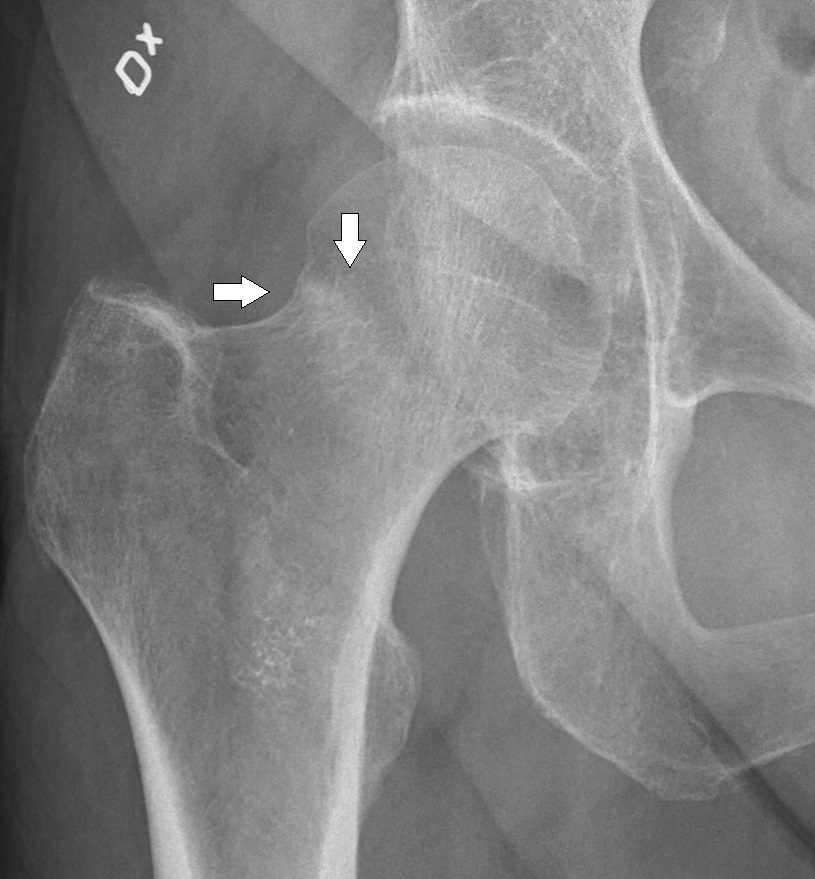

Labeled plain radiograph demonstrating a subtle compressive hip fracture.